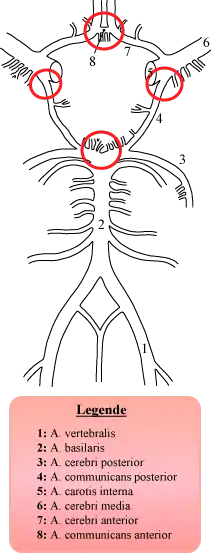

The circle of Willis (also called Willis' circle, loop of Willis, cerebral arterial circle, and Willis polygon) is a circulatory anastomosis that supplies blood to the brain and surrounding structures in reptiles, birds and mammals, including humans.[1] It is named after Thomas Willis (1621–1675), an English physician.[2]

The circle of Willis is a part of the cerebral circulation and is composed of the following arteries:[3]

- Anterior cerebral artery (left and right) at their A1 segments

- Anterior communicating artery

- Internal carotid artery (left and right) at its distal tip (carotid terminus)

- Posterior cerebral artery (left and right) at their P1 segments

- Posterior communicating artery (left and right)

Variation

Considerable anatomic variation exists in the circle of Willis, with classic anatomy seen only in about one-third of people.[5] In one common variation the proximal part of the posterior cerebral artery is narrow and its ipsilateral posterior communicating artery is large, so the internal carotid artery supplies the posterior cerebrum; this is known as a fetal posterior communicating cerebral artery. In another variation the anterior communicating artery is a large vessel, such that a single internal carotid supplies both anterior cerebral arteries; this is known as an azygos anterior cerebral artery.[6]